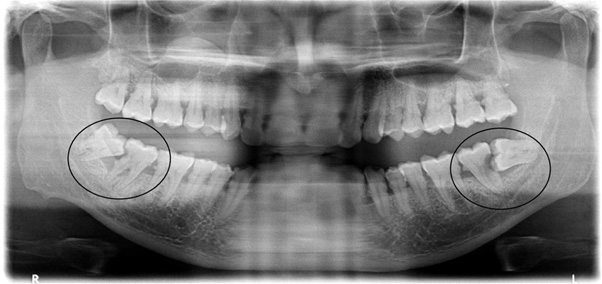

Poorly aligned wisdom teeth can have a positioning that creates a trap for plaque and debris between the wisdom tooth and the next molar ahead (the 2nd molar). Because these traps of debris cannot be cleansed properly not only is the wisdom tooth is placed at risk for developing decay but the next molar is also, as seen in picture above.

X-rays of the wisdom teeth are made to help assess the positions, shapes and sizes of the crowns and roots, the surrounding bone and the nerve which usually runs below the roots of the teeth.

X-rays also help in identification of associated conditions such as cysts in relation to the teeth, apart from aiding in planning of the surgical extraction procedure.